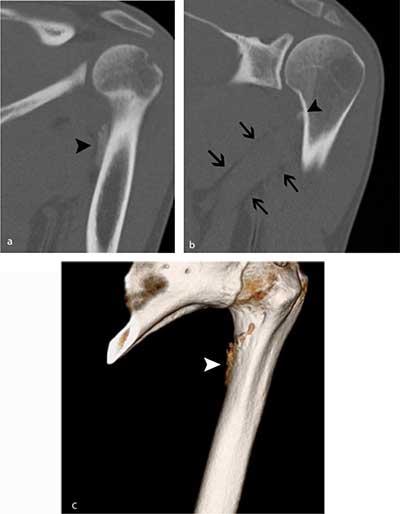

Figure 4

Follow-up CT five weeks later. a) Oblique coronal reformatted image of the proximal humerus shows a slightly more dense aspect of the periphery of the calcification (black arrowhead). b) MIP reconstructions (1.5 mm) clearly show that the calcification is located at the medial crest of the lesser tuberosity (black arrowhead). Note also the perimuscular fat pads surrounding the teres major muscle (black arrows). c) Volume Rendering Technique (VRT) image revealing irregular contour (white arrowhead) near the medial crest of the lesser tuberosity.